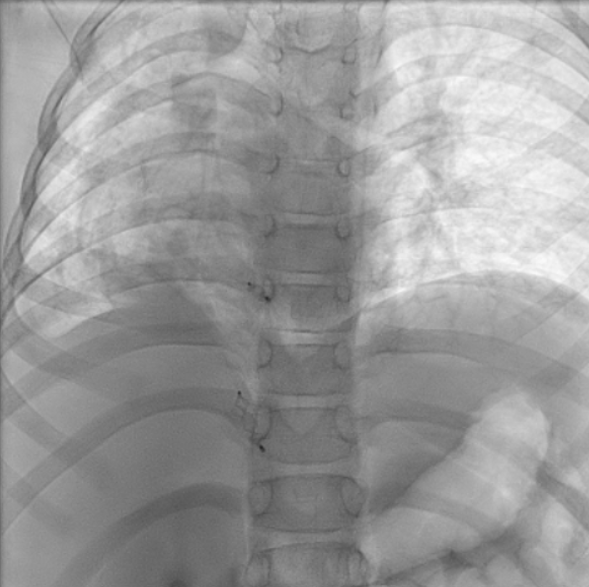

Following resolution of pneumonia, the child underwent cardiac catheterization, which confirmed dual arterial supply to the right lung via the right pulmonary artery and APCs. It was decided to redirect flow and reduce shunting using vascular plugs. First, femoral access was obtained with a 5F catheter. Next, a digital subtraction aortogram was performed with a 5F pigtail catheter. The prominent APC from the DTA measured 3.1 mm; it was hooked with a 5F Judkins right (JR) guiding catheter. A 4 x 6-mm Amplatzer Vascular Plug II (Abbott) was then deployed into the APC under angiographic guidance. The APC from the celiac artery measured 3.2 mm; it was hooked with a 5F JR guiding catheter. A 6 x 6-mm Amplatzer Vascular Plug II was deployed into the APC under angiographic guidance. The prominent APCs were successfully occluded (Figure 3), and post-deployment angiogram showed good position and good flows in the celiac artery and its other branches (Video 2).